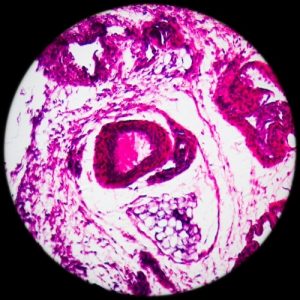

Под названием «лимфома» объединяют различные виды злокачественных поражений лимфатической системы. Одни из них склонны к быстрому росту и распространению, другие менее агрессивны. Прогноз лечения во многом зависит от того, какой вид лимфомы диагностирован. Например, при лимфоме Ходжкина прогнозы наиболее благоприятны, особенно у детей, при неходжкинских лимфомах, которых больше 30 видов, прогноз определяется степенью злокачественности.

- Биопсию.